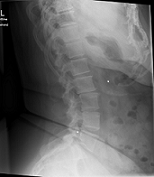

Röntgenbilder

- TSPINE

- TSPINE vk II.png (22.24 KiB) 19749 mal betrachtet

deine Bilder lassen vermuten, dass vielleicht gar nicht die Skoliose dein Problem ist, sondern dein sagittales Profil. (Steht dein Kopf ziemlich nach vorne, wenn du dich vin der Seite betrachtest?) solltest auf jeden Fall einmal zum Spezialisten, im deine Situation kompetent abklären zu lassen. Aus NRW ist wahrscheinlich Dr. Verres in Bingen am nächsten.

mit dem sagittalen Profil meint man das Profil von der Seite gesehen. Laut deinen Aufnahmen hast du eher eine geringe Skoliose, aber einen ziemlichen Rundrücken und Hohlkreuz was auch Beschwerden machen kann und das die Ärzte auch gerne übersehen oder nicht sehen wollen. Deshalb ist es auch wichtig, einen Spezialisten aufzusuchen, der dies auch mit behandeln kann. Leider ist dies keine Ganzaufnahme, dann würde man das eher sehen. Es gibt hier schon genug Berichte, die das mit Hyperkyphose und -lordose gut beschreiben. Also lesen bildet...